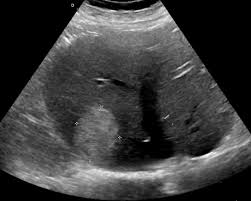

What is the finding?

Sludge